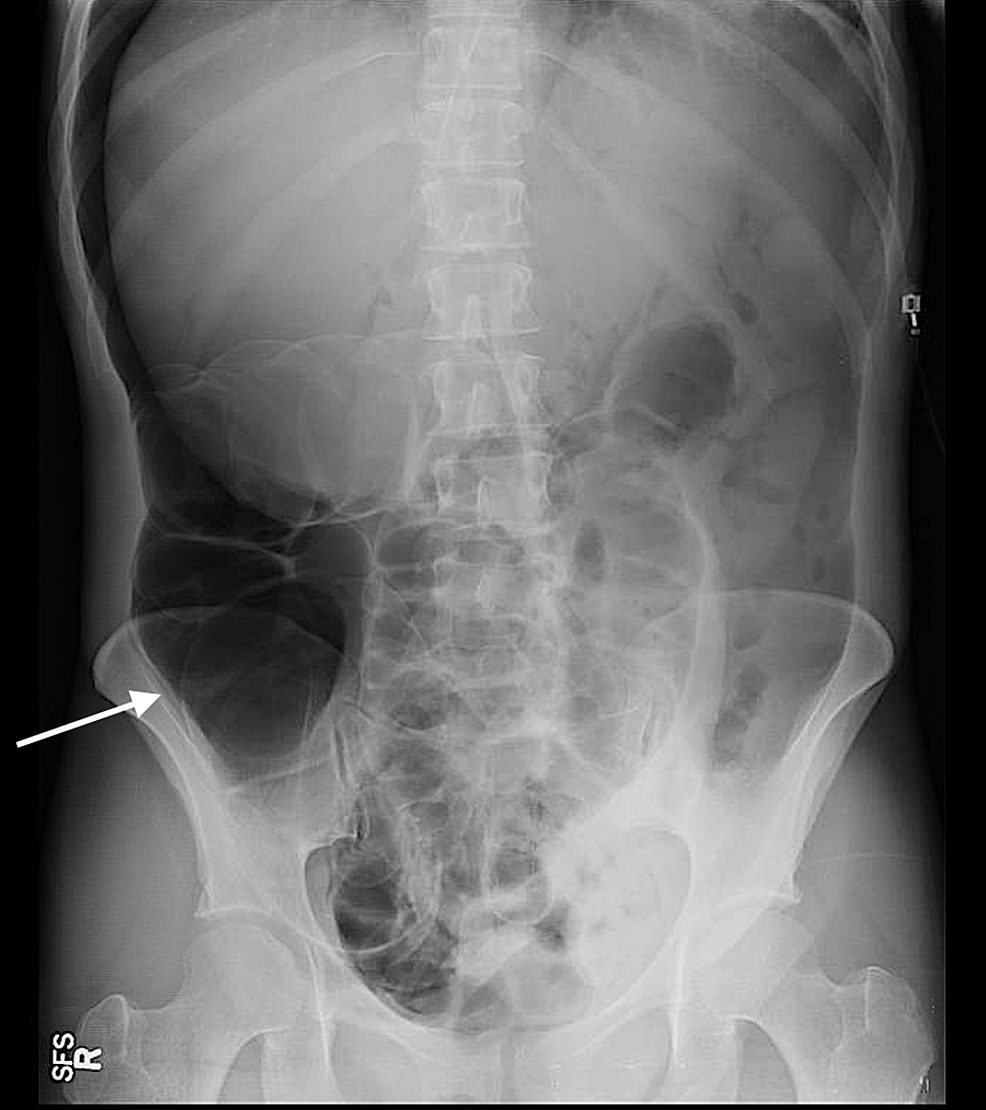

The patient’s history dates back to one year prior when she had presented with similar complaints. At that time, the patient complained of watery diarrhea, left lower quadrant abdominal pain, and fecaluria for one month. Her stool clostridium difficile antigen test was first obtained and it came back positive. The urine drug screen was positive for cocaine and methamphetamines. A computed tomography (CT) scan of the abdomen was done that showed a segmental colitis involving the sigmoid colon and small fistulous tract extending from the sigmoid colon towards the bladder dome (Figure 1).